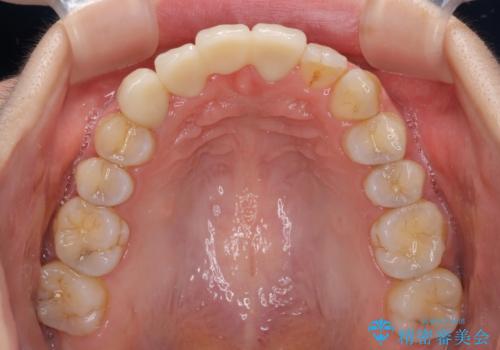

補助装置により上顎歯列を遠心移動させたため、非抜歯でしたが口元の突出感をある程度改善させることができました。

欠けてしまった前歯もオールセラミッククラウンにて自然に補綴することができました。